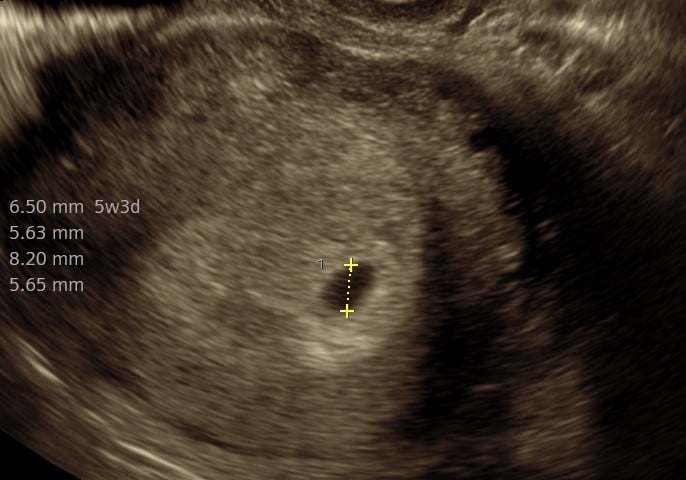

Praksisjordemoders tidlige tryghedsscanning (uger 5+0‑7+0) giver dig muligheden for:

- at bekræfte graviditet i livmoderen,

- at se hjerteblink, fra 6+3

- at få en foreløbig terminsberegning og stille spørgsmål til jordemoderen.